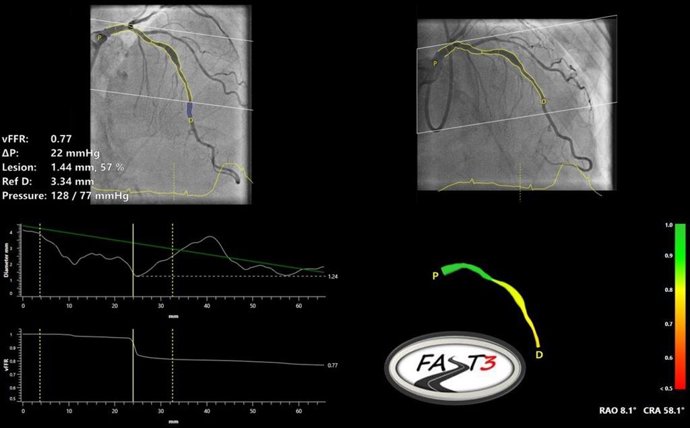

CAAS vFFR Software

MAASTRICHT, Países Bajos, 18 de junio de 2024 /PRNewswire/ -- Pie Medical Imaging, líder mundial en imágenes cardíacas, anunció la finalización de la inscripción en FASTIII, un ensayo clínico aleatorizado multicéntrico que investiga el uso de la reserva fraccional de flujo vascular basada en angiografía (CAAS vFFR) en pacientes sometidos a procedimientos de revascularización coronaria. vFFR puede evaluar si el estrechamiento de una arteria coronaria es funcionalmente significativo y puede requerir revascularización.

FASTIII es el ensayo de no inferioridad más grande en ejecución (inscribió a 2228 pacientes), en el que se compara una estrategia guiada por vFFR derivada angiográficamente con una estrategia guiada por FFR para guiar la revascularización coronaria. El criterio de valoración principal es una combinación de muerte por todas las causas, cualquier infarto de miocardio o cualquier revascularización 1 año después de la aleatorización.